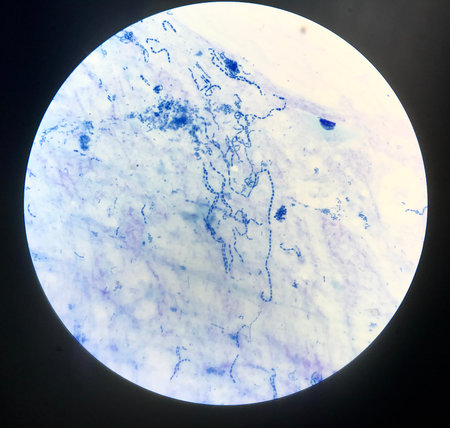

gram stian was show gram positive bacilli.